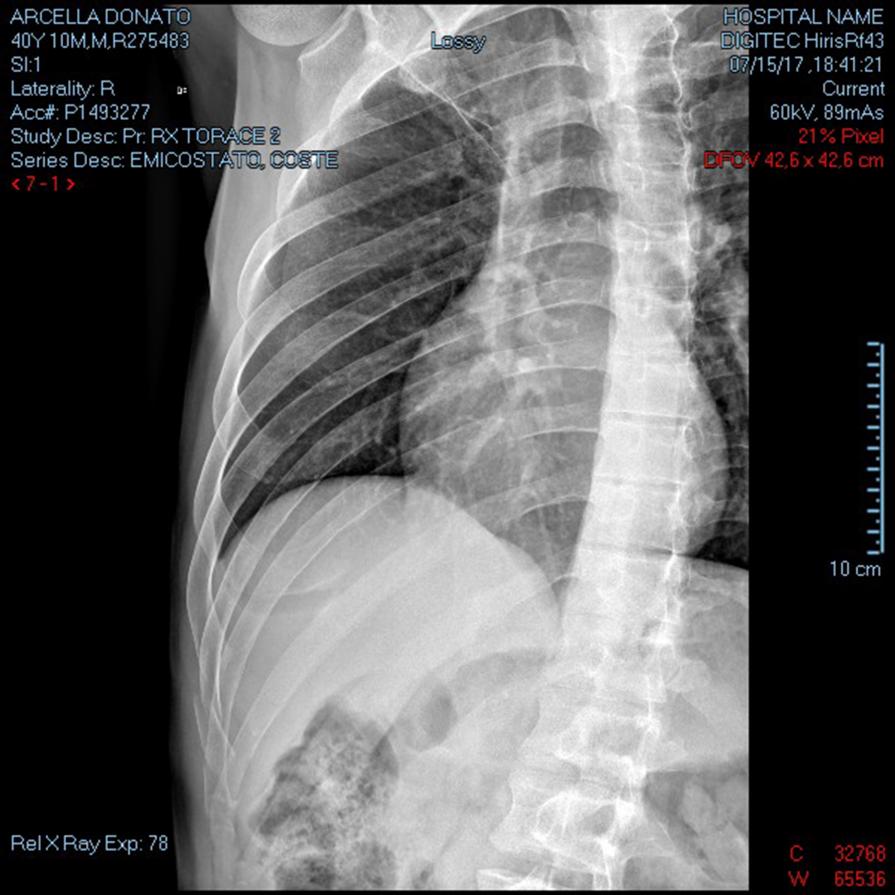

Emitorace DX ( autoritratto radiografia )

RX EMICOSTATO DX RX TORACE 2 PROIEZIONI RX TORACE ESPIRIUM Frattura lievemente scomposte all'arco posteriore della XI E XII costa e frattura scomposta all'arco anteriore dell'VIII costa dal lato destro, Frattura sostanzialmente composta all'arco medio-anteriore della X costa. Non evidenti falde pneumiche. Non apprezzabili versamenti pleurici né alterazioni parenchimali focali...